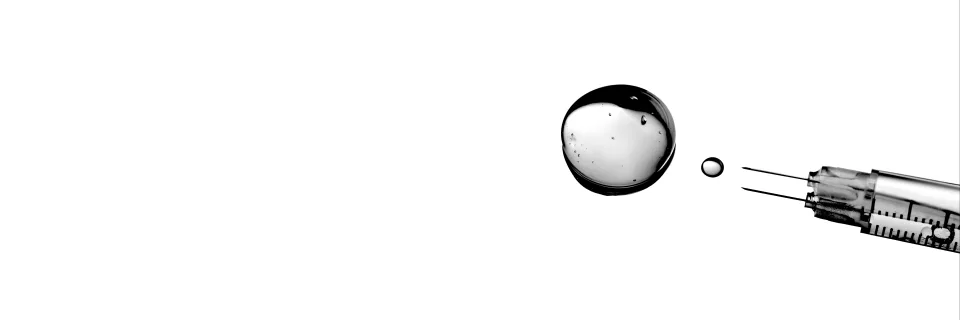

PromaDerm – Exzellenz in jeder Spritze

PromaDerm, eine Sparte der PromaMedical GmbH, ist Ihr spezialisierter Einzel- & Großhandelspartner für hochwertige Injectables in der ästhetischen Dermatologie. Wir bieten ausschließlich Produkte etablierter und renommierter Hersteller, die sich in der Praxis durch ihre Qualität und vorhersehbare Wirksamkeit bewährt haben.